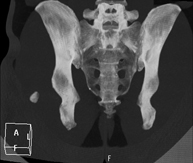

- TC Pelvis Prueba diagnóstica que consiste en obtener imágenes bi y tridimensionales de la pelvis de alta definición anatómica (estructuras óseas, estructuras vasculares, vejiga, útero y ovarios, próstata y vesículas seminales, uréteres, etc.) mediante el empleo de un equipo de TC (Tomografía Computarizada). La mayoría de estudios requieren el empleo de contraste yodado. Prueba diagnóstica que consiste en obtener imágenes bi y tridimensionales de la pelvis de alta definición anatómica (estructuras óseas, estructuras vasculares, vejiga, útero y ovarios, próstata y vesículas seminales, uréteres, etc.) mediante el empleo de un equipo de TC (Tomografía Computarizada). La mayoría de estudios requieren el empleo de contraste yodado.

- TC Pelvis ósea Exploración radiológica que mediante un sistema de rayos X y detectores que giran alrededor del paciente, reconstruyendo las imágenes por ordenador (TC Multidetector), permite el estudio de huesos, músculos y articulaciones de la pelvis. Exploración radiológica que mediante un sistema de rayos X y detectores que giran alrededor del paciente, reconstruyendo las imágenes por ordenador (TC Multidetector), permite el estudio de huesos, músculos y articulaciones de la pelvis.